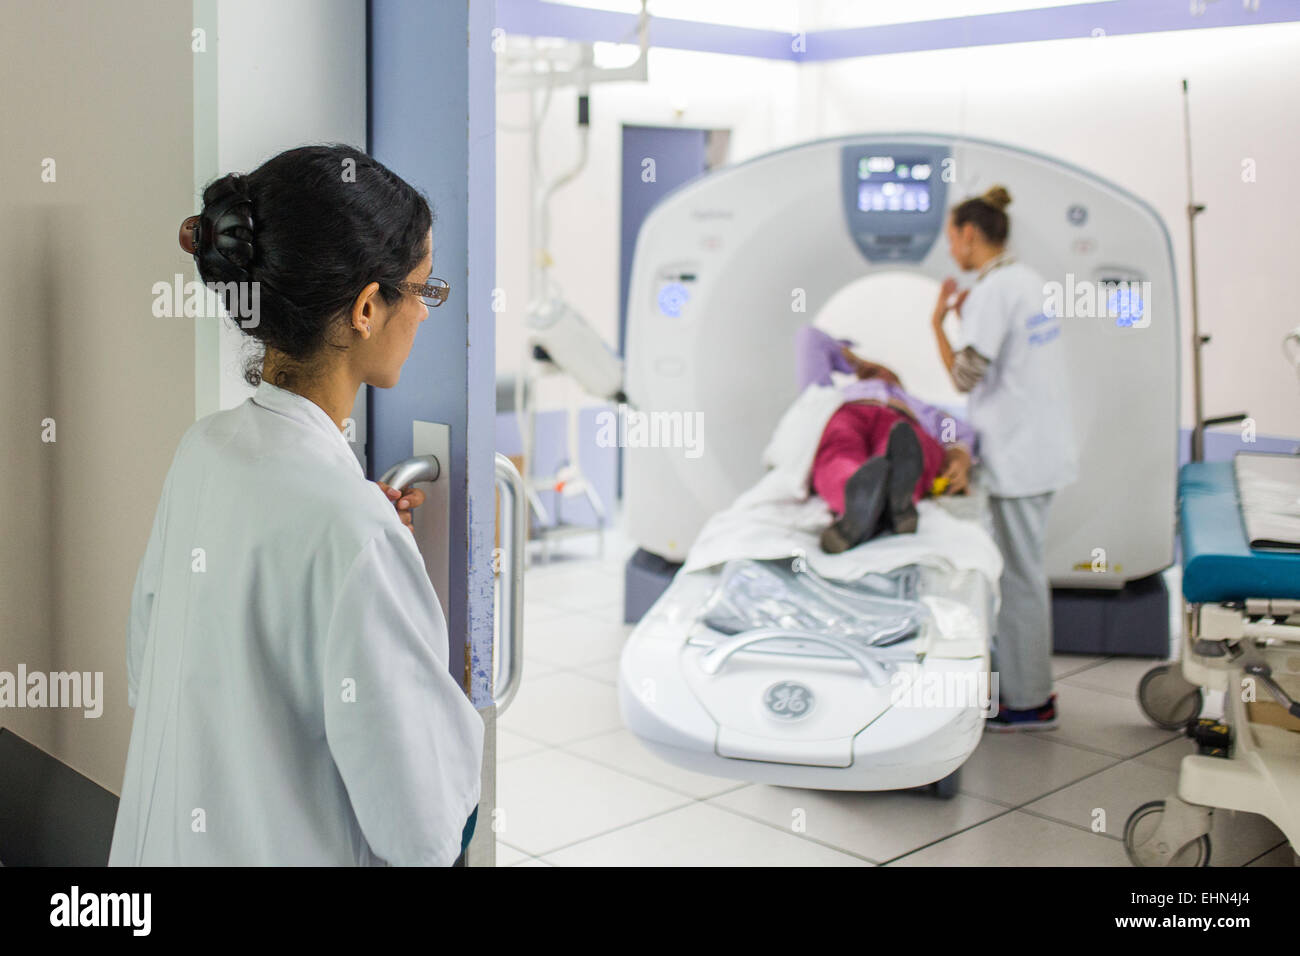

La TDM cérébrale, l'hôpital d'Angoulême, France . Banque D'Imageshttps://www.alamyimages.fr/image-license-details/?v=1https://www.alamyimages.fr/photo-image-la-tdm-cerebrale-l-hopital-d-angouleme-france-72441773.html

La TDM cérébrale, l'hôpital d'Angoulême, France . Banque D'Imageshttps://www.alamyimages.fr/image-license-details/?v=1https://www.alamyimages.fr/photo-image-la-tdm-cerebrale-l-hopital-d-angouleme-france-72441773.htmlRME5T065–La TDM cérébrale, l'hôpital d'Angoulême, France .

Un scanner du cerveau, l'hôpital de Bordeaux, France. Banque D'Imageshttps://www.alamyimages.fr/image-license-details/?v=1https://www.alamyimages.fr/photo-image-un-scanner-du-cerveau-l-hopital-de-bordeaux-france-79755264.html

Un scanner du cerveau, l'hôpital de Bordeaux, France. Banque D'Imageshttps://www.alamyimages.fr/image-license-details/?v=1https://www.alamyimages.fr/photo-image-un-scanner-du-cerveau-l-hopital-de-bordeaux-france-79755264.htmlRMEHN4J8–Un scanner du cerveau, l'hôpital de Bordeaux, France.

Un scanner du cerveau, l'hôpital de Bordeaux, France. Banque D'Imageshttps://www.alamyimages.fr/image-license-details/?v=1https://www.alamyimages.fr/photo-image-un-scanner-du-cerveau-l-hopital-de-bordeaux-france-79755262.html

Un scanner du cerveau, l'hôpital de Bordeaux, France. Banque D'Imageshttps://www.alamyimages.fr/image-license-details/?v=1https://www.alamyimages.fr/photo-image-un-scanner-du-cerveau-l-hopital-de-bordeaux-france-79755262.htmlRMEHN4J6–Un scanner du cerveau, l'hôpital de Bordeaux, France.

Un scanner du cerveau, l'hôpital de Bordeaux, France. Banque D'Imageshttps://www.alamyimages.fr/image-license-details/?v=1https://www.alamyimages.fr/photo-image-un-scanner-du-cerveau-l-hopital-de-bordeaux-france-79755260.html

Un scanner du cerveau, l'hôpital de Bordeaux, France. Banque D'Imageshttps://www.alamyimages.fr/image-license-details/?v=1https://www.alamyimages.fr/photo-image-un-scanner-du-cerveau-l-hopital-de-bordeaux-france-79755260.htmlRMEHN4J4–Un scanner du cerveau, l'hôpital de Bordeaux, France.

Patient subissant une tomodensitométrie (TDM) du cerveau (accident vasculaire cérébral (AVC)), l'hôpital de Bordeaux, France. Banque D'Imageshttps://www.alamyimages.fr/image-license-details/?v=1https://www.alamyimages.fr/photo-image-patient-subissant-une-tomodensitometrie-tdm-du-cerveau-accident-vasculaire-cerebral-avc-l-hopital-de-bordeaux-france-79755235.html

Patient subissant une tomodensitométrie (TDM) du cerveau (accident vasculaire cérébral (AVC)), l'hôpital de Bordeaux, France. Banque D'Imageshttps://www.alamyimages.fr/image-license-details/?v=1https://www.alamyimages.fr/photo-image-patient-subissant-une-tomodensitometrie-tdm-du-cerveau-accident-vasculaire-cerebral-avc-l-hopital-de-bordeaux-france-79755235.htmlRMEHN4H7–Patient subissant une tomodensitométrie (TDM) du cerveau (accident vasculaire cérébral (AVC)), l'hôpital de Bordeaux, France.